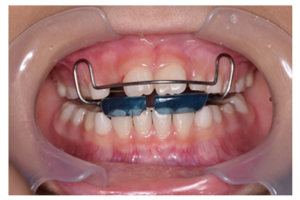

ファンクショナルアプライアンスとは

ファンクショナルアプライアンスは、顎の成長をコントロールするための装置です。成長期の子どもに使用され、顎の位置を適切に誘導することで、正常な噛み合わせを形成します。リップバンパーもその一種として含まれます。

使用目的と効果

- 下顎前歯の唇側移動: 口唇の圧力を排除することで、前歯を前方に移動させる。

- 永久歯の萌出スペース確保: 将来の歯の生えるスペースを作る。

- 反対咬合の改善: 噛み合わせの不正を矯正する。